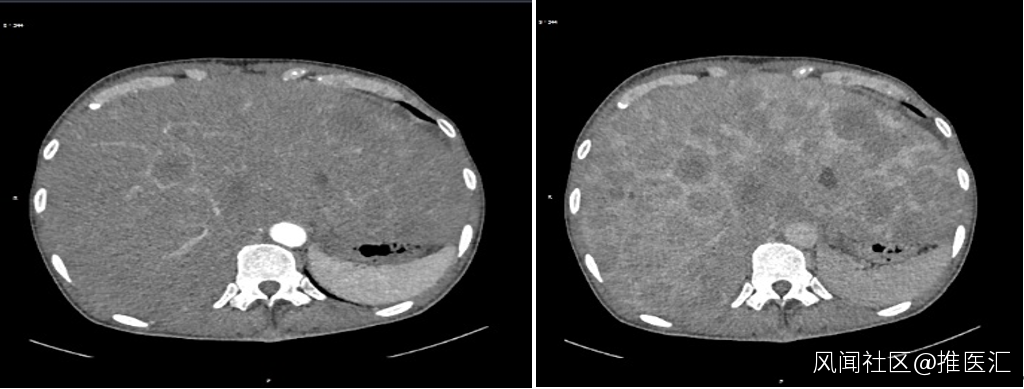

圖2:腹部強化CT圖片;A.動脈期;B.門脈期

強化CT的結果發現食管佔位,肝臟多發轉移癌。肝臟穿刺活檢的病理結果提示為惡性腫瘤,形態像是小細胞癌,需要做免疫組織化學檢測進一步確定。